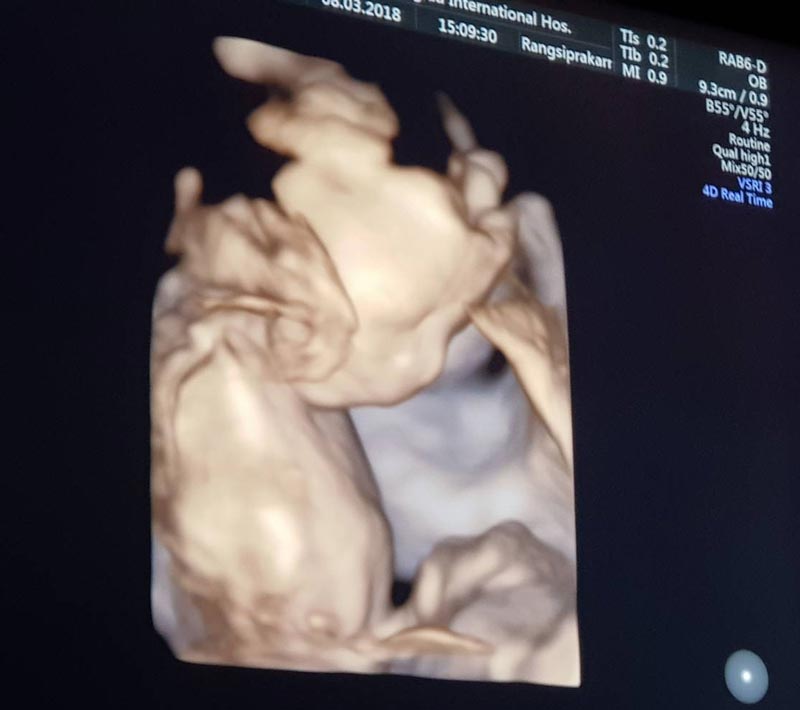

"ในที่สุดลูกชายแม่ก็มา ขอบคุณสวรรค์ที่มอบลาภอันประเสริฐมาให้ ดีใจที่สุดเลย #ฟินเวอร์ #น้ำตาคลอ แม่ซึ้งเห็นผู้ชายแล้วน้ำตาไหล ... เป็นเรื่องราวดี ๆ ที่เข้ามาอีกเรื่องในชีวิต ขอบคุณทุกๆคำอวยพรจากทุกๆคนนะคะ แม่ฟินมากกกกกกกพูดเลยยยย #20weekspregnant #welcomemyboy สามีพี่ยิ้มกว้างมากกกกก @por_tnp"